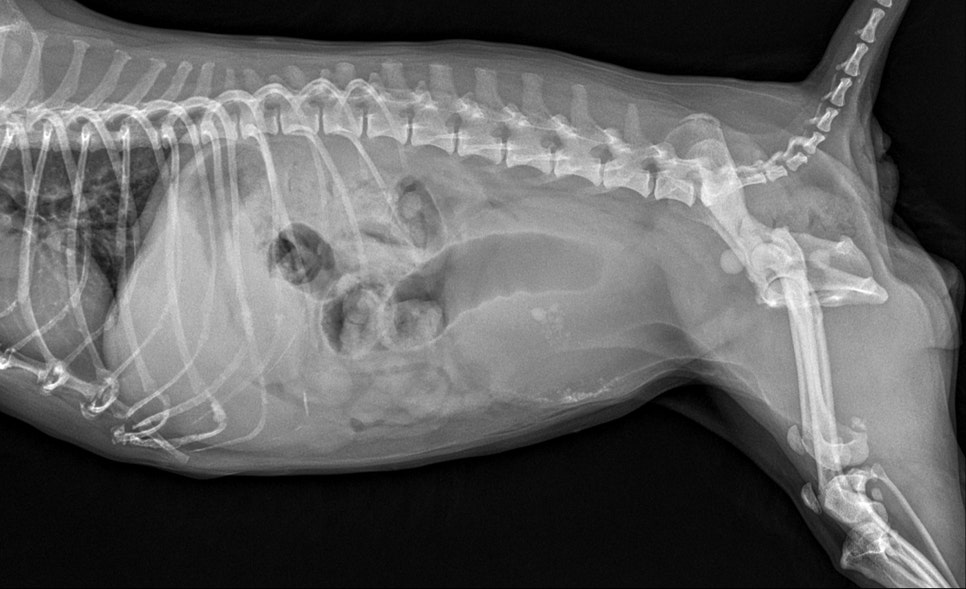

내원 당시 방사선 검사 결과 / 출처: 24시온숲동물의료센터

응급 진료 후 방사선(X-ray)과 초음파 검사 결과, 요도를 막고 있는 큰 결석이 확인되었으며, 이 결석이 요도를 막고 있어 소변 배출이 불가능한 상태였습니다.